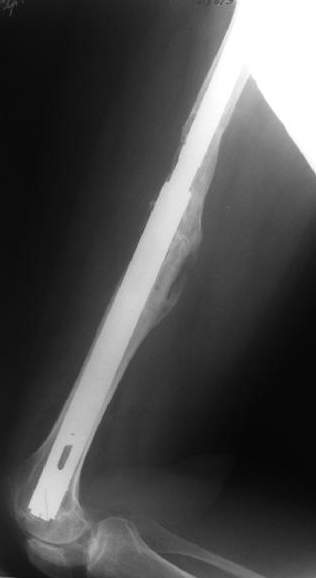

Female, rheumatoid, THA in 2003, car accident in 2006, failed plating. Nailing in Oct 2007. The nail is solid with hollow proximal part where the stem is docked. Last images are in 1 year after

nailing.

THX for the discussion. After few days of traction by ex-fix the surgery was performed. An attempt of closed nailing was unsuccesful because of fragment translation, which was blocked by cement fragments. After removal of broken cement pieces reduction was reached "automagically". Also some cement from lateral part was removed by

chisel to expose distal 40-50 mm of the stem to allow tight fit of the nail. Further fixation by the nail was pretty easy and straightforward. Images attached. The stem looked stable in its proximal part both laterally and medially. Comments/critics are welcome.